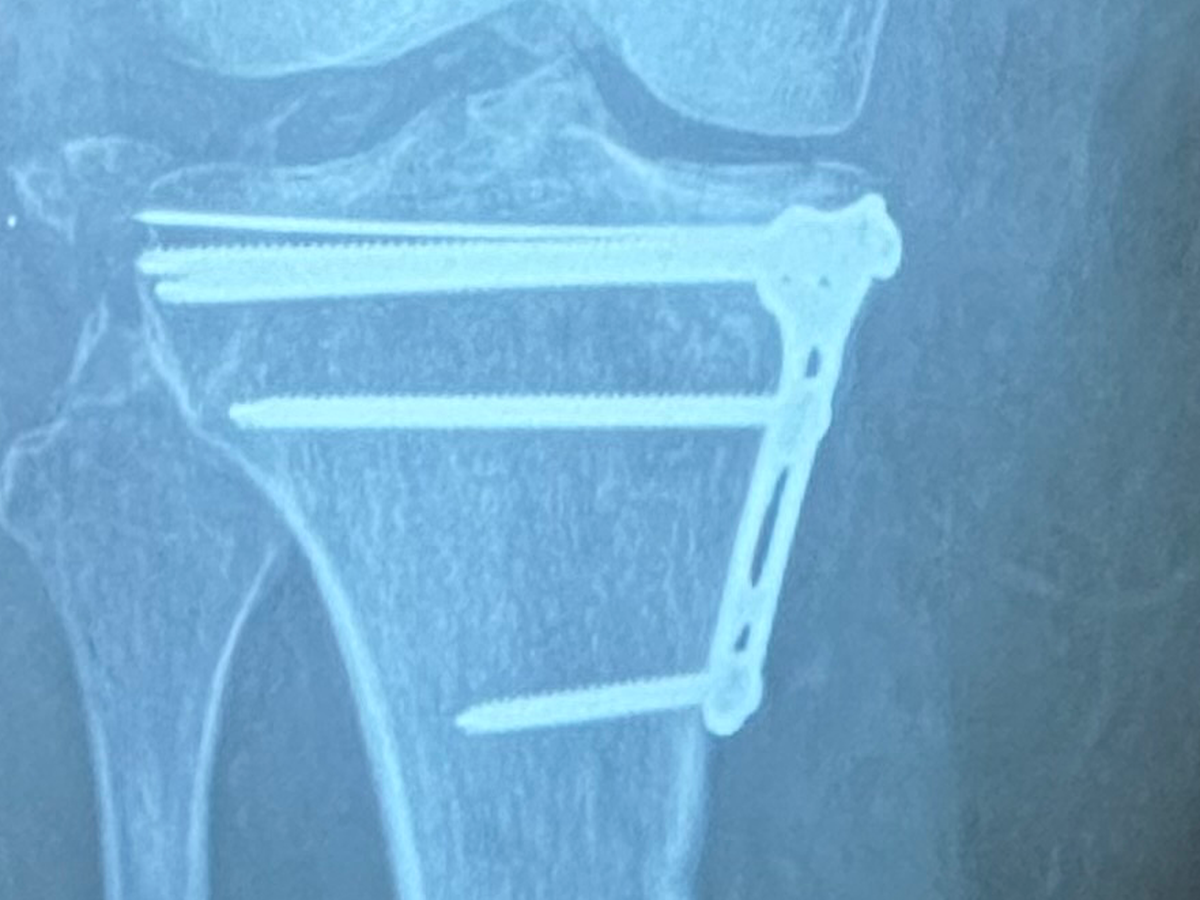

Hello! My name is Stephanie and I’m here posting on behalf of myself and my husband. Not many people know, but I’ve been out of work for almost a year due to breaking my tibia plateau in multiple pieces, tearing all of the ligaments in my leg, and having nerve damage to my foot in March of 2024. Due to the severity of my injury, this has financially put a huge burden on our household. I have been unable to return to work because I’m a server and it is an unsafe environment for me considering I still at this time have stability issues. We are literally drowning in bills and paycheck to paycheck, on one person's income, is not even touching the tip of the iceberg. I am here, last resorting to this page to attempt to put us back on our feet again. Any little bit would help, even if it’s just a dollar. ❤️ Thank you!

Today I got news that I might potentially be having surgery again. The outlook was not what I was hoping for, but it’s probably my best option moving forward. Recovery looks like another long process, and there’s not much more we can do but accept the outcomes ahead of us. I’m just trying to stay hopeful that I make the right decision moving forward for my long term health.